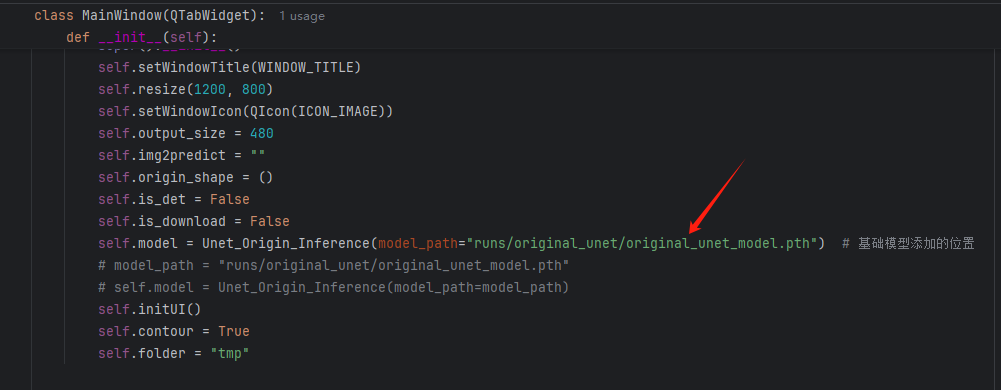

如果你是训练了自己的模型,请在下面的位置进行切换。

系统支持医学图像的分割、轮廓的查找以及简单的病例的记录。